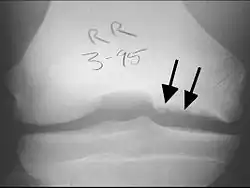

X-rays show lucency of the ossification on the anterior aspect of the knee in juvenile patients. In older people, the lesion typically appears as an area of osteosclerotic bone with a radiolucent line between the osteochondral defect and the epiphysis. The visibility of the lesion depends on its location and on the amount of knee flexion used. Harding described the lateral X-ray as a method to identify the site of an OCD lesion.[36]